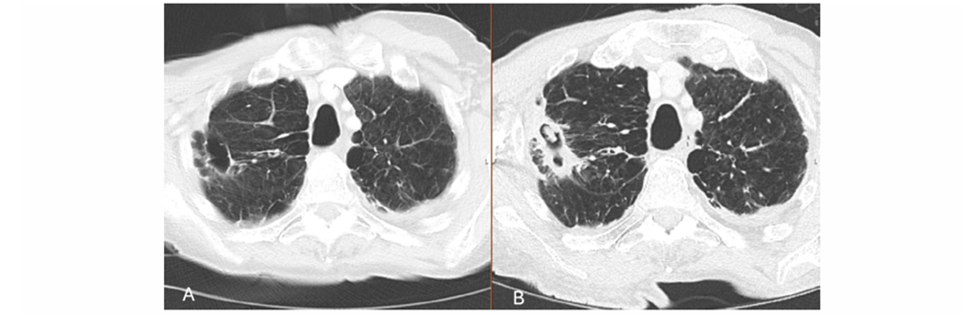

Clínicamente las recaídas pueden ser sutiles, con mínimo empeoramiento de los síntomas, pero con cambios significativos a nivel radiológicos o de la función pulmonar. Por lo tanto, el seguimiento debe incluir imagenologíca, titulación de IgG anti-Aspergillus, y cultivos fúngicos de pulmón y de esputo.

(B) Un año después de haber suspendido el tratamiento antifúngico, la TC muestra reaparición de bolas fúngicas dentro de la cavidad, engrosamiento de las paredes de la cavidad y consolidaciones pulmonares adyacentes.